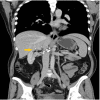

Figure 7

Figure 7. Post-operative CT scan (coronal view) at the one-month follow-up

The image is showing clips at the surgical bed (yellow arrow) with no evidence of recurrence or metastases.